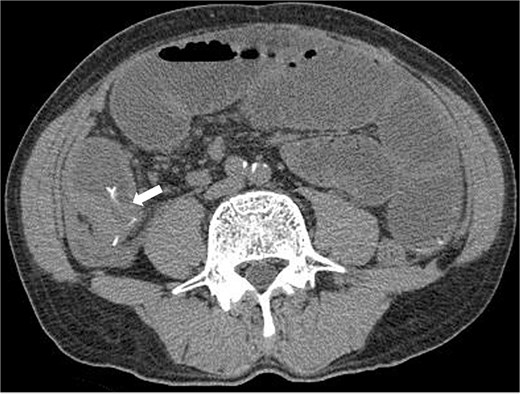

A 63-year-old man presented with recurrent right lower abdominal pain. Blood tests showed mildly elevated C-reactive protein (CRP), dehydration, and a high alpha-fetoprotein (AFP) of 2659 ng/ml. Computed tomography (CT) revealed a high-density area in the small intestine of the right lower abdomen, which was suspected to be a foreign body, with circumferential wall thickening in the same area (Fig. 1). The intestinal tract on the oral side of the area was dilated, and small intestinal obstruction due to chronic inflammation caused by the foreign body was suspected.

Preoperative CT revealed a high density area in the small intestine of the right lower abdomen, which was suspected to be a foreign body, and a circumferential wall thickening in the same area. The intestinal tract on the oral side of the area was dilated, and small intestinal obstruction due to chronic inflammation caused by the foreign body was suspected.